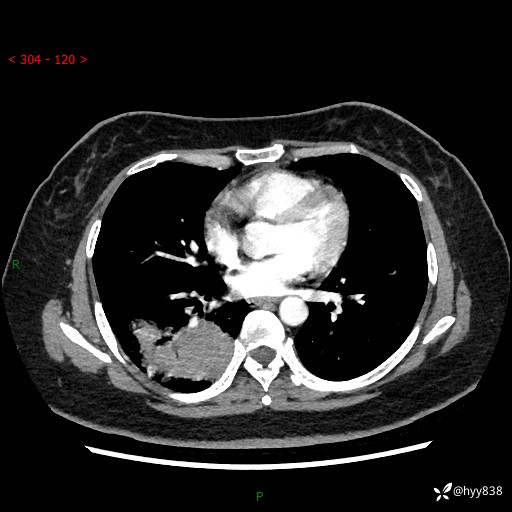

增强动脉期+静脉期